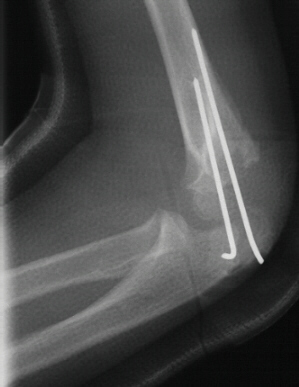

- TREATMENT: The patient was taken to the operating room where under

general anesthesia and tourniquet control the fracture was exposed utilizing

an anterolateral approach, taking care not to disturb the posterior vascular

pedicle of the lateral condyle. Following adequate reduction of the fracture,

2 diverging k-wires were placed across the fracture site.

The

patient was immobilized in a long arm cast at 90 degrees until radiographic

evidence of healing was apparent. The long arm cast and k-wires were removed

in clinic.